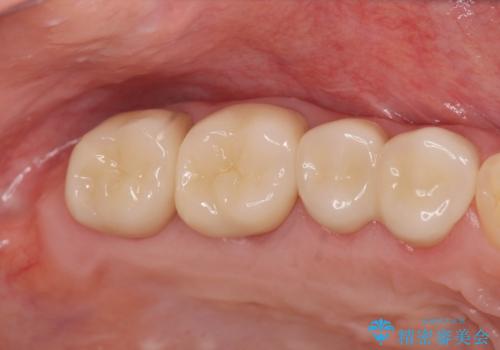

虫歯の再発可能性を限りなく低く抑えるためには、虫歯の徹底的な除去を行ったのちの精度の高いセラミック治療が必須です。

今回の治療では歯ぐきの問題を解決するため、歯周外科を行いました。